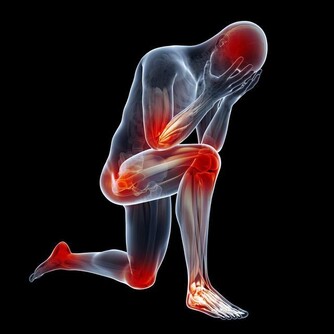

很多人飽受膝關節疼痛折磨甚至影響到日常生活。以下四種人需要重視這篇文章:關節嘎巴嘎巴響的人;腿疼的人;上下樓腿疼、膝蓋疼,有骨刺;O型腿的。

膝關節冷、上下樓梯疼、軟弱無力等,這都是常見的膝關節問題。

一、年齡問題。膝蓋就像是榫卯結構一樣,榫卯用久了會不合套。關節用了十幾年的膝關節出問題也是正常。

二、膝關節這地方血管很少,它受損一般都是磨損、乾澀導致的,不會淤血。所以內服藥物很難解決問題。